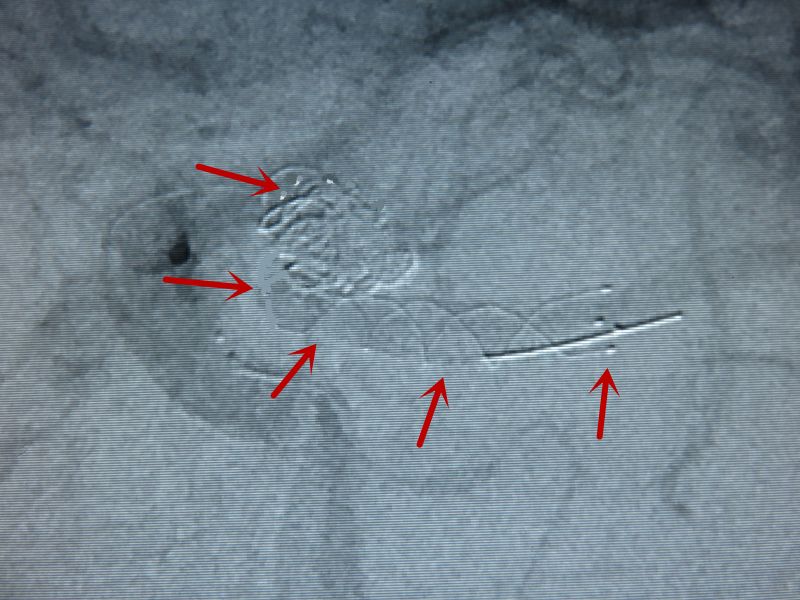

额极动脉与M1成反折的锐角,多次微导管塑形技术超选失败,后使用成袢技术顺利超选。

微导管在M1段成“∝”状,微导丝超选进瘤腔。

此时与常规操作不同,不是前推而是回撤微导管,随着微导管进入瘤腔,同步撤微导丝进入微导管内。

恰如足球的倒钩射门一样。

顺利栓塞动脉瘤。